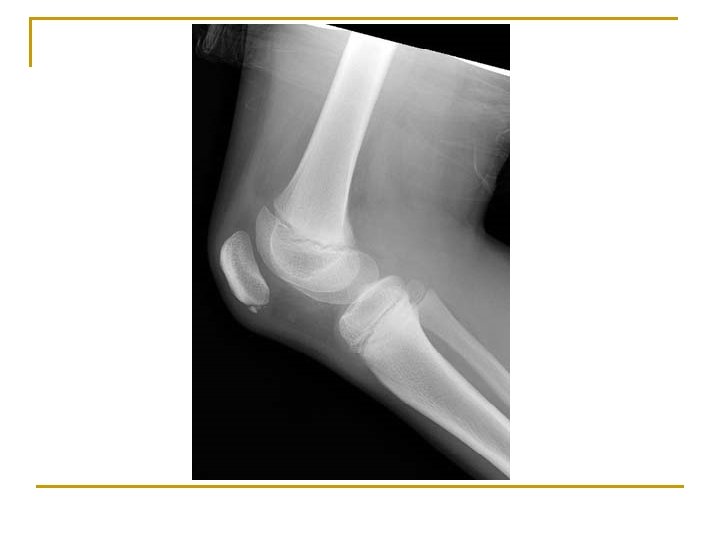

Osgood-Schlatter’s Disease n n n Cause: common in immature athletes. Repeated pull of the patellar tendon at the tibial tubercle. S/S: Swelling, hemorrhage, and gradual degeneration of tubercle (causing deformity) TX: Conservative: RICE (ice cups) n n n Out for 6 months to 1 year Rehabilitation ST: X-Ray